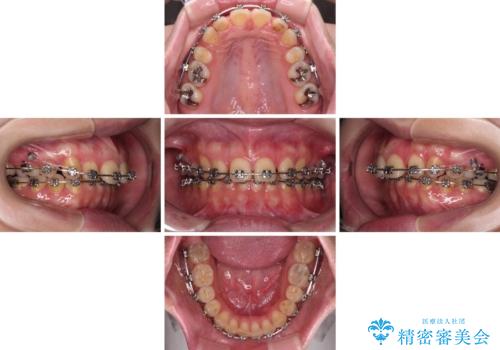

- 矯正装置

- メタルブラケット

- 治療期間

- 4年

- 治療回数

- 30回以上

4年程度はかかるとの想定でしたが、予定通り4年ちょうどで治療を終えることができました。

上顎前歯の歯軸が大きく改善され、横顔の印象が改善されました。